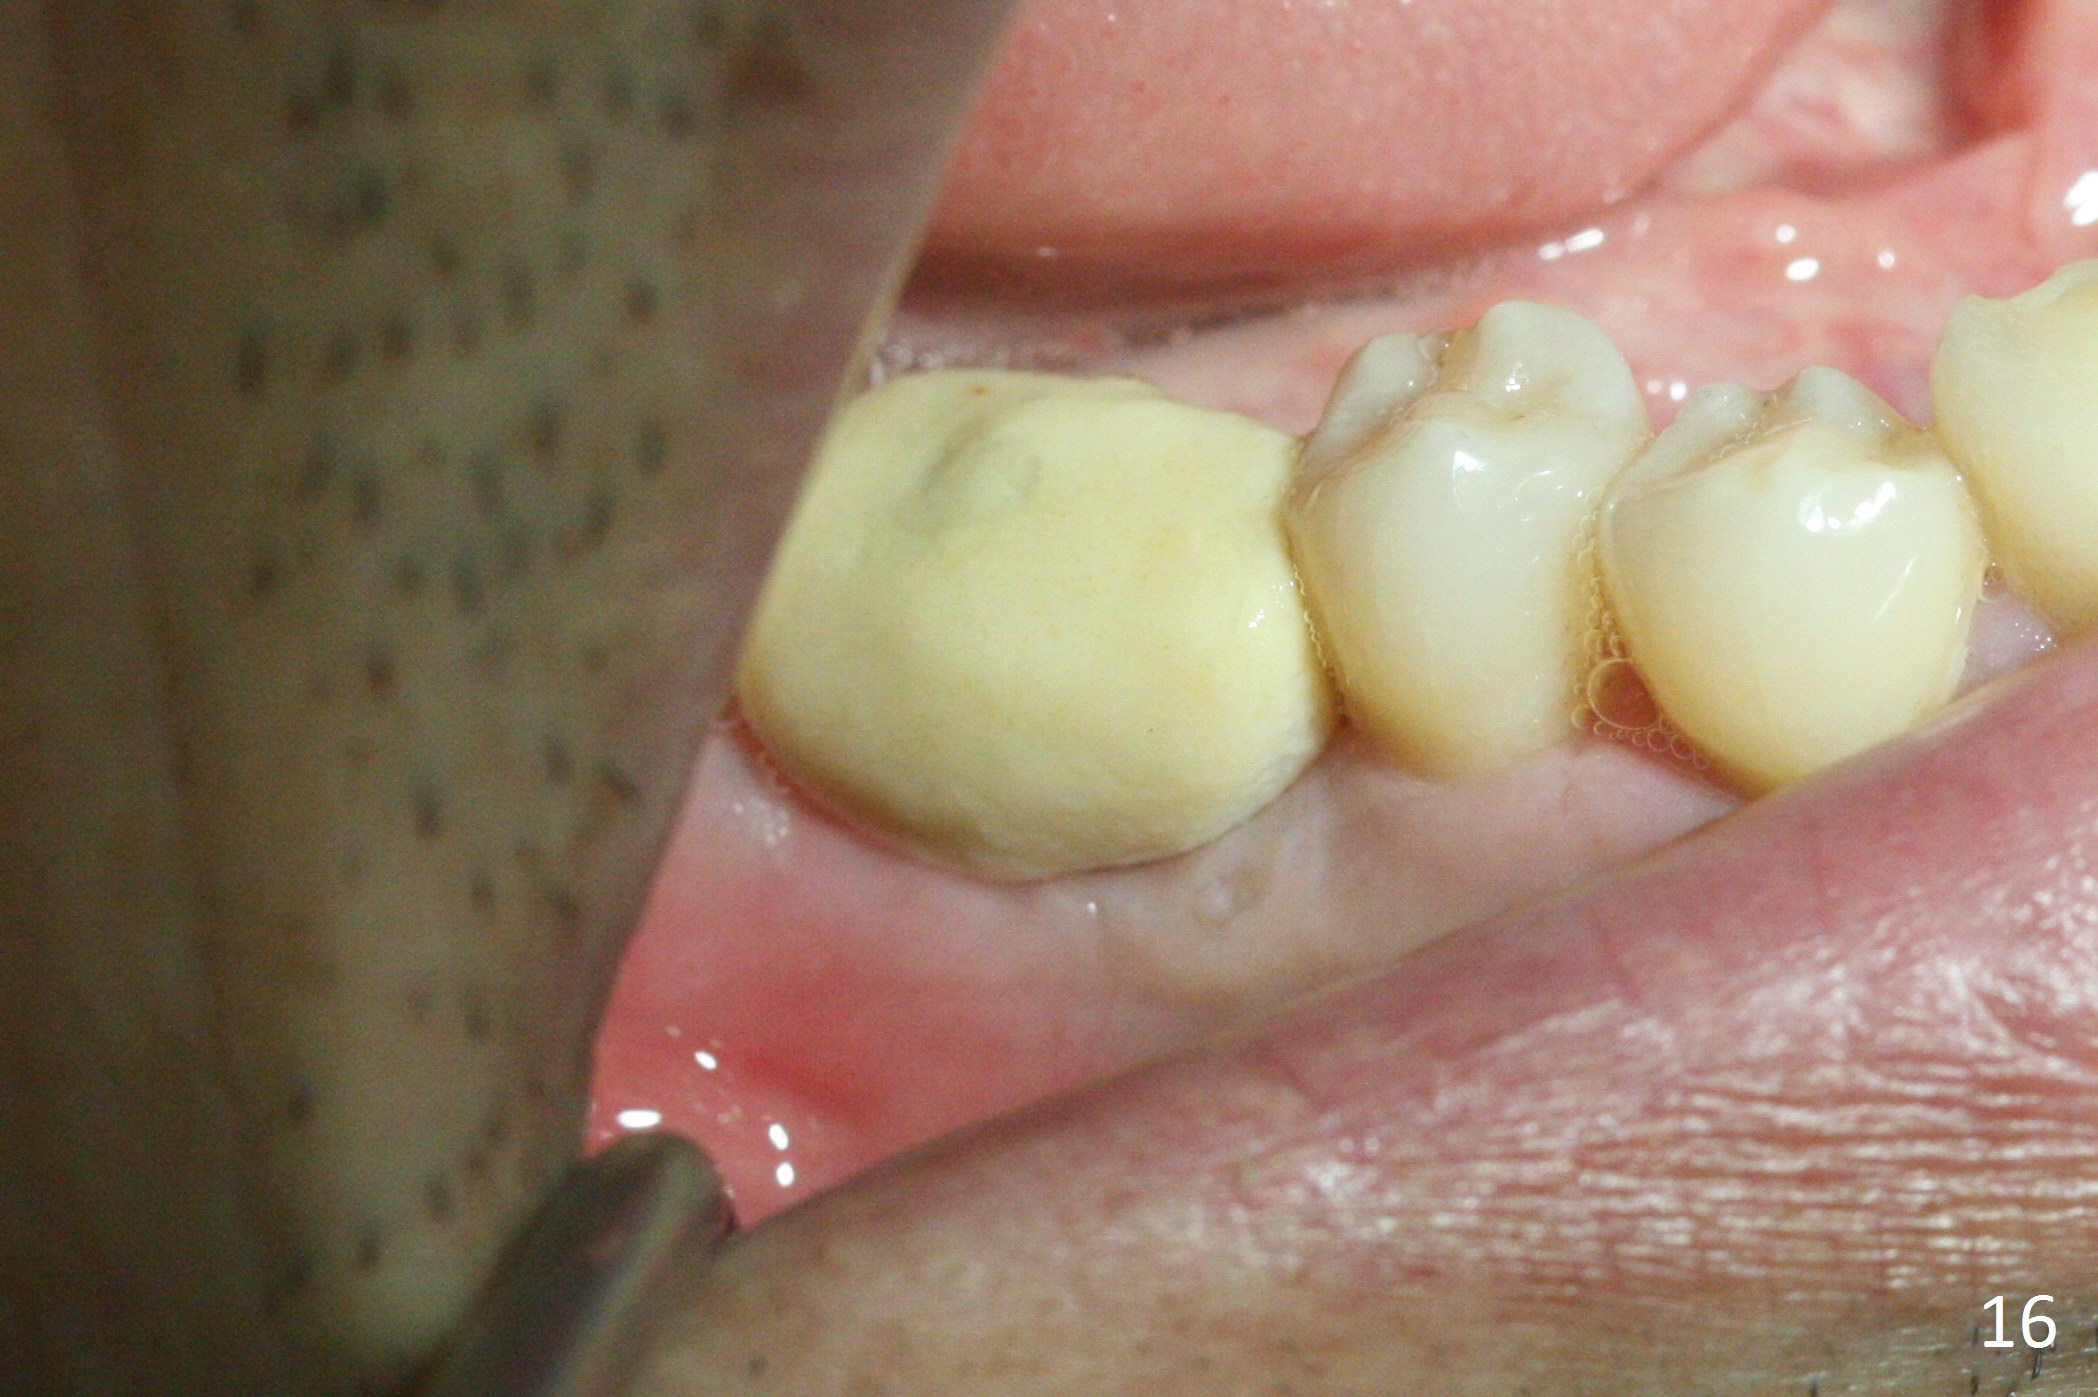

Implant threads appear to have been covered by bone coronally (Fig.15 *) and apically (<) 5 months postop. The provisional remains in place (Fig.16), although dislodged twice and replaced by the patient. The gingiva around the provisional and abutment is healthy (Fig.17 after packing with gingival retraction cord for impression).